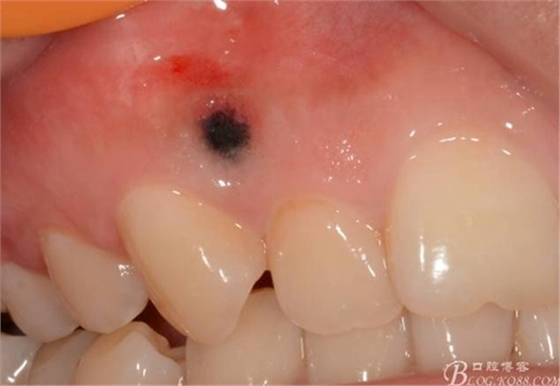

0.8*17mm工作尖 100mj 20Hz去除上皮,暴露著色區(qū)

1.0-1.3*17mm工作尖 100mj 25-30Hz去除色素后即刻